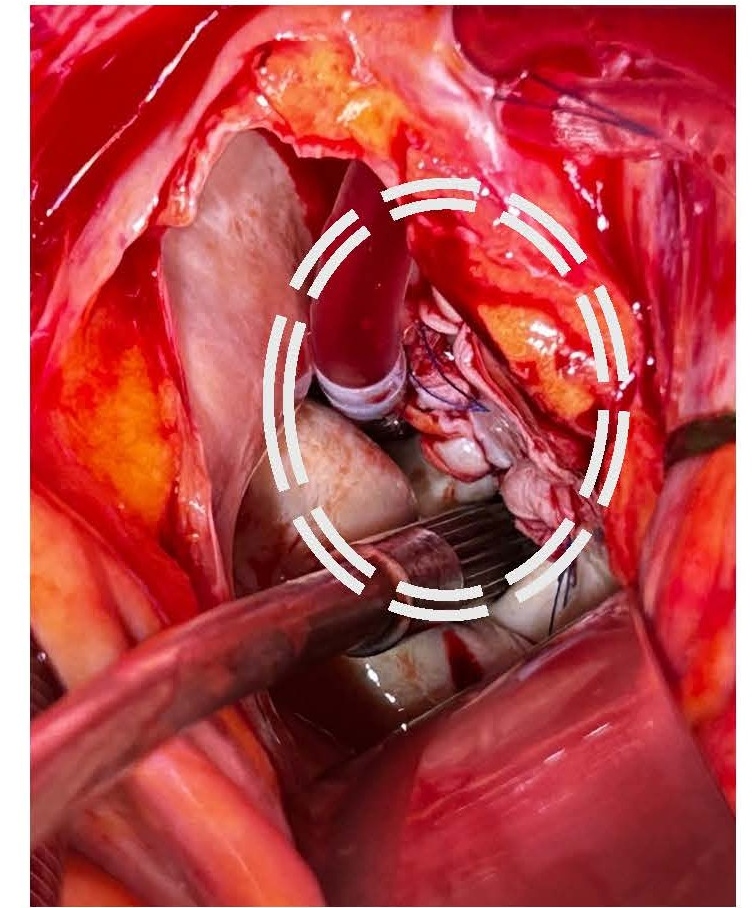

Given the severe clinical presentation, a decision was made to proceed with urgent cardiothoracic surgery on post-ablation day 26. Left atriotomy revealed a substantial vegetation associated with a necrotic fistulous orifice of approximately 1.5 cm in diameter located on the posterior wall of the left atrium near the left pulmonary vein ostia (Figures 5 and 6). The vegetation was resected, and purulent secretions were expressed from the fistulous orifice. Cultures of these samples later showed contamination with Staphylococcus aureus and Streptococcus anginosus. The fistulous orifice was closed using an autologous pericardial patch (Figure 7).

Figure 7. Repair of the fistula with pericardial patch.

Following atriotomy closure, a first aortic declamping was directly associated with massive esophageal bleeding, which was externalized through the patient's mouth. A second aortic clamping and a new atriotomy were performed to make a plication of the base of the left atrium to ensure the seal of the fistulous orifice. The second aortic declamping did not show any further esophageal bleeding. The aortic clamping and cardiopulmonary bypass times were 111 and 146 minutes, respectively. Cardiac conduction recovery was delayed, requiring the placement of ventricular pacemaker leads.